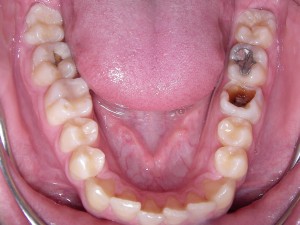

Auf dem Bild ist die Entstehung von Karies = Zahnloch in zunehmenden Stufen zu sehen:

Von rechts nach links: Karies beginnt mit einem weissen Fleck (entkalkter Schmelz), der einbricht und weiches braunes Dentin offenlegt. Jetzt ist eine Reparatur = Füllung fällig. Der große Backenzahn hat bereits eine Amalgamfüllung. Übrigens: Dieser Patient hat vorne (rechts im Bild) seine Zähne besser gereinigt als weiter hinten. Deshalb entstand der größte Zahnschaden am hinteren Backenzahn (links im Bild). Und noch eine Erkenntnis: Weil der Zahnbelag in der Rinne zwischen Zahn und Zahnfleisch nicht so gut entfernt wurde wie auf den Glattflächen der Zähne, gibt es folgerichtig genau in dieser Rinne die Defekte. Da wo die Zähne gut von der Zahnbürste gereinigt wurden, strahlen sie, dass man fast eine Sonnenbrille braucht! 😉